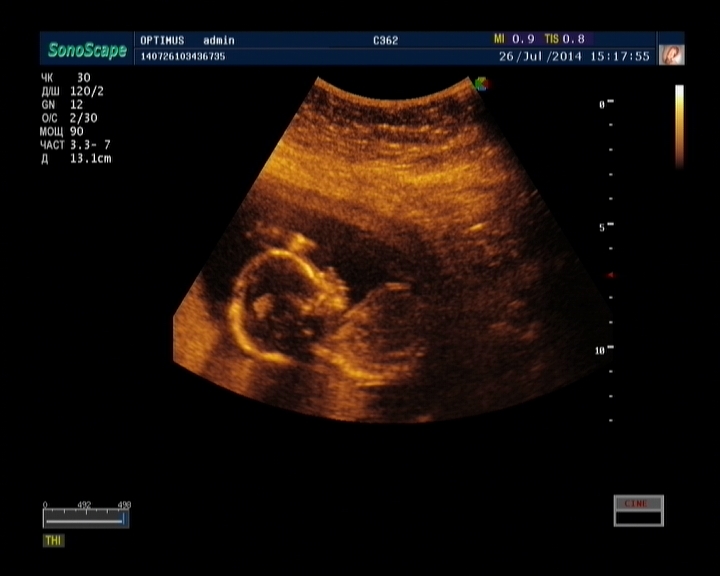

Наш мальчик превратился в доченьку))))))))))))))))))

Всё о нашей беременностиВот так)))))))Только приехали с узи,делали видео запись.Ну думаю так для интереса дай спрошу кто у нас,сама то знаю что мальчик на 2-х узи сказали))))А она мне так уверена ДЕВОЧКА,мы с мужем переглянулись и улыбаемся)))) Потом она долго искала перчик,но нет,там точно пирожок!))))))))))))Я конечно сначала оболдела,ведь я вещичек уже прикупила и имя выбрали(Платоном хотели назвать).Ну а теперь МЕГА счастливы с мужем!!!!!!Я со дня переноса чувствовала что доча,но когда на узи говорили пацан,я решила что моя интуиция хреновая,а нет,оказалась я права))))Имя для доченьки было изначально,назовем Варенька)

Узистка сказала что доченька "даст нам прикурить",она пипец какая крутливая,катается колобком во мне,мы были в шоке,я даже напугалась что она что-нить себе сломает))))))Эмоции конечно не передаваемые)))А еще нам сказали что у нее очень милые черты лица  в маму красотка будет)))))))))))))

А вот и мы))